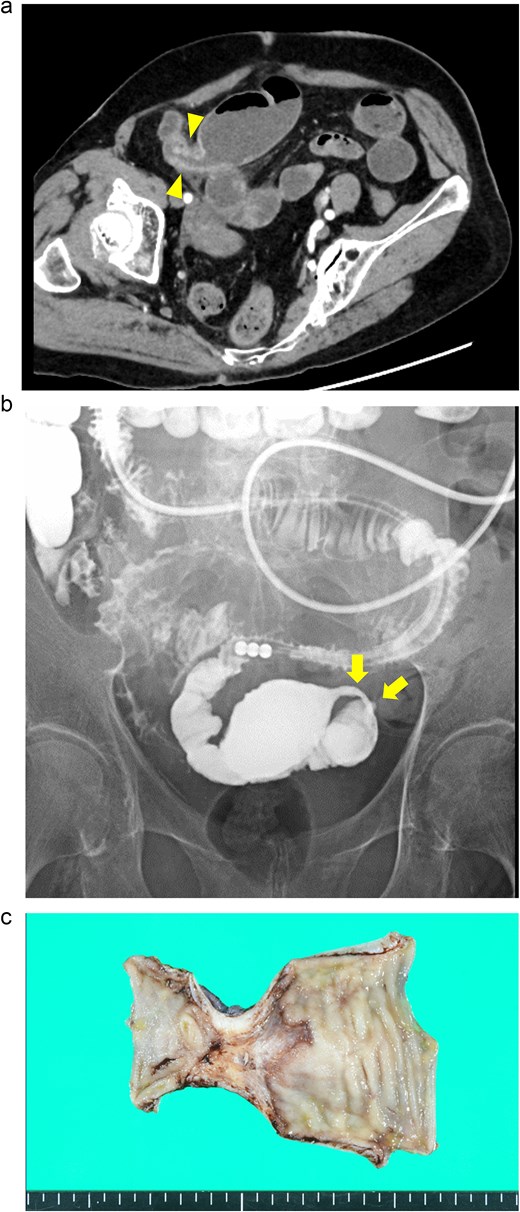

A 76-year-old man presented with a gradual onset of intermittent epigastric and left abdominal pain. Three months prior, he experienced similar pain, and computed tomography (CT) revealed hepatic portal venous gas (HPVG) without mesenteric ischemia or bowel strictures. The patient’s symptoms resolved with conservative treatment, none of the CT features during follow-up. His vital signs were stable, and laboratory test results were normal, including a white blood cell (WBC) count of 8800/μl, C-reactive protein (CRP) concentration of 0.02 mg/dl, hemoglobin (Hb) level of 12.5 g/dl, and lactate (Lac) concentration of 0.7 mmol/l. CT enterography revealed a segmental stricture with wall thickening in the distal ileum (Fig. 1a). Double-balloon endoscopy (DBE) revealed a circumferential ulcer and segmental stricture in the distal ileum. Fluoroscopy during DBE confirmed segmental, smooth luminal narrowing in the distal ileum (Fig. 1b).

Case 1: (a) CT enterography with water-soluble contrast agent. The arrowheads indicate a segmental stricture with wall thickening in the distal ileum. (b) Fluoroscopy during double-balloon endoscopy. The arrows indicate a segmental, smooth luminal narrowing in the distal ileum. (c) Macroscopic view of the resected specimen. Circumferential ulceration is visible in the affected area.

Exploratory laparoscopy revealed a 10-cm-long segmental bowel stricture with wall thickening 50 cm from the ileocecal valve, which was resected. The pathological specimen revealed a circumferential ulcer with granulation tissue at the stenotic site, accompanied by edematous mucosa and fibrotic submucosa in the surrounding areas. No signs of tumors or inflammatory bowel disease (IBD) were noted (Fig. 1c). The postoperative course was uneventful, and the patient was discharged on the ninth postoperative day. By the 10-month follow-up, he had not had any recurrences of abdominal symptoms.